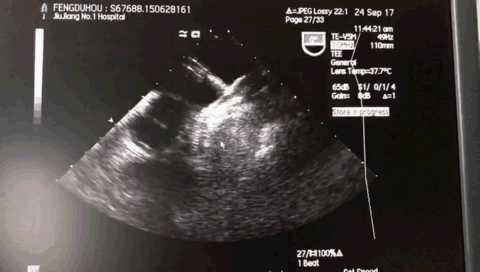

术前超声:

术中超声:

TEE 0:

TEE 45:

TEE 135牵拉试验: